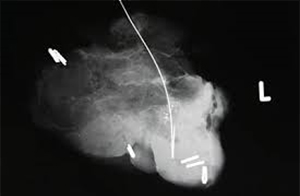

Βιοψία - αφαίρεση αποτιτανώσεων, ασβεστώσεων μαστού (εικόνα Γ)

Σε περίπτωση που οι αποτιτανώσεις κρίνονται λιγότερο ή περισσότερο ύποπτες πρέπει να γίνει αφαίρεσή τους. Η αφαίρεση αυτή μπορεί να γίνει με τον κλασσικό τρόπο στο χειρουργείο μετά από τη στερεοτακτική τοποθέτηση κάποιου σύρματος ή ραδιοϊσοτόπου, δεδομένου ότι οι αποτιτανώσεις είναι συνήθως αψηλάφητες. Ο χειρουργός αφαιρεί την περιοχή οδηγούμενος από το σύρμα. Ακολουθεί μαστογραφία παρασκευάσματος την ώρα του χειρουργείου για να είμαστε σίγουροι ότι έχουν αφαιρεθεί όλες οι αποτιτανώσεις. Αυτός είναι ο ογκολογικά πιο σωστός τρόπος. Σε περίπτωση που οι αποτιτανώσεις είναι λιγότερο ύποπτες, η ασθενής είναι νέα και δεν υπάρχει σημαντικό οικογενειακό ιστορικό, μπορεί η αφαίρεση να γίνει και στερεοτακτικά υπό μαστογραφικό έλεγχο με τοπική αναισθησία. Το πλεονέκτημα αυτής της μεθόδου είναι ότι δεν είναι κανονικό χειρουργείο με τομή και γενική νάρκωση.

Γίνεται με τη χρήση χοντρής βελόνας υπό τοπική αναισθησία και με τη βοήθεια συστήματος κενού αέρος για τη λήψη περισσότερου υλικού. Τα μειονεκτήματα της μεθόδου είναι η υποεκτίμηση της βλάβης (δηλαδή να θεωρηθεί στην ιστολογική πιο "αθώα" η βλάβη απ' ό,τι είναι πραγματικά), η δημιουργία αιματώματος και ο συμβιβασμός στην ογκολογική εξαίρεση, όσον αφορά στον καθορισμό των υγειών ορίων. Επίσης, κάποιες ατυπίες μπορούν να διαχωριστούν από καρκίνους χαμηλής επιθετικότητας μόνο αν γίνει πλήρης αφαίρεση της βλάβης. Σε περίπτωση που η ιστολογική εξέταση της βλάβης δείξει κάποιο καρκίνο πρέπει να ακολουθήσει κανονικό χειρουργείο.

Εικόνα Γ

Μαστογραφία παρασκευάσματος βιοψίας κατόπιν εντοπισμού με συρμάτινο οδηγό.

Εδώ φαίνεται ένα μικρό τμήμα μαστού με ύποπτες αποτιτανώσεις που αφαιρέθηκε.

Φαίνεται, επίσης, η άκρη του σύρματος με το αγκίστρι στην άκρη του που μας

καθοδήγησε να βρούμε το μαστογραφικό εύρημα που δεν ψηλαφούσαμε.